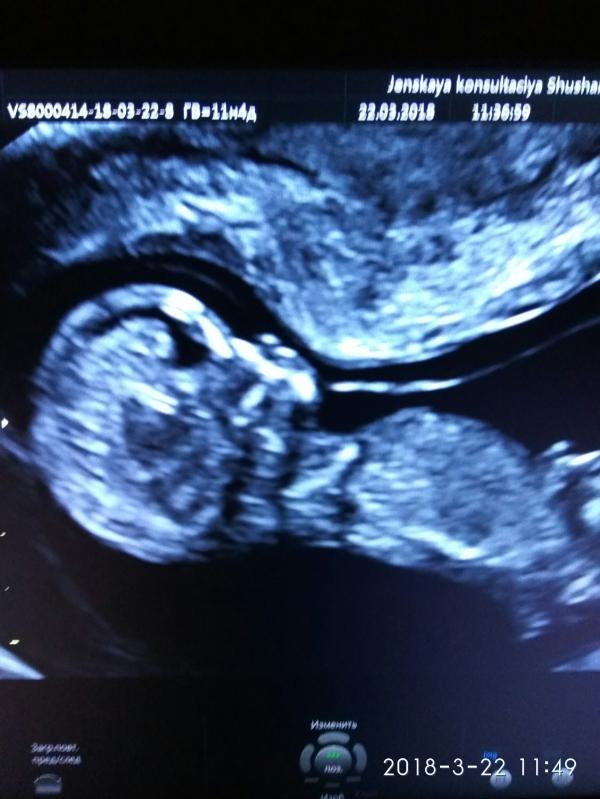

Девочки, сегодня в первые увидела свое счастье) какое это счастье 😄 делюсь с вами )))

@maru1804 поздравляю! Супер фото 😍

А в 9 недель уже так видно?? Я забыла все напрочь🙈 поздрпвляю

@katrin.etrange делала УЗИ в поликлинике в Шушарах,врач Шпилевая Т. И.